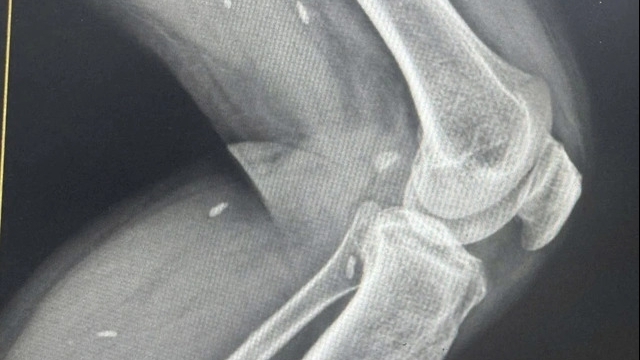

Thông tin từ bệnh viện trung ương Thái Nguyên cho biết: Bệnh nhân M.V.D. (45 tuổi, Võ Nhai, Thái Nguyên) bị bừa đâm vào mặt ngoài đầu gối phải, đã vệ sinh và khâu vết thương. Sau đó, vết thương sưng to, chảy dịch phải nhập viện và được chẩn đoán nhiễm trùng gói phải. Bệnh viện cho điều trị kháng sinh 10 ngày với Ceftizoxim + Tobramycin. Sau đó, vết thương khô nên bệnh nhân được ra viện.

Đến 10 ngày sau, ông D. lại nhập viện trở lại với tình trạng vết thương chảy dịch mủ hình thành ổ áp xe. Bệnh viện đã phẫu thuật, nạo tổ chức viêm lấy xương chết và nuôi cấy mủ. Kết quả cấy mủ cho thấy, ông D. bị nhiễm khuẩn gram âm Burkholderia pseudomallei hay còn gọi là khuẩn ăn thịt người gây bệnh Whitmore.

Sau 3 tuần, vết thương vùng gối phải khô, liền sẹo tốt, bệnh nhân ra viện tiếp tục điều trị kháng sinh duy trì theo phác đồ.